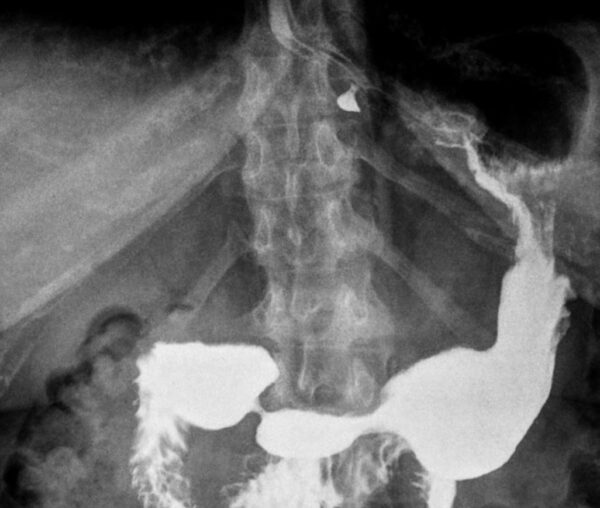

https://radiopaedia.org/cases/epiphrenic-diverticulum-2

FLUOROSCOPY

GIT